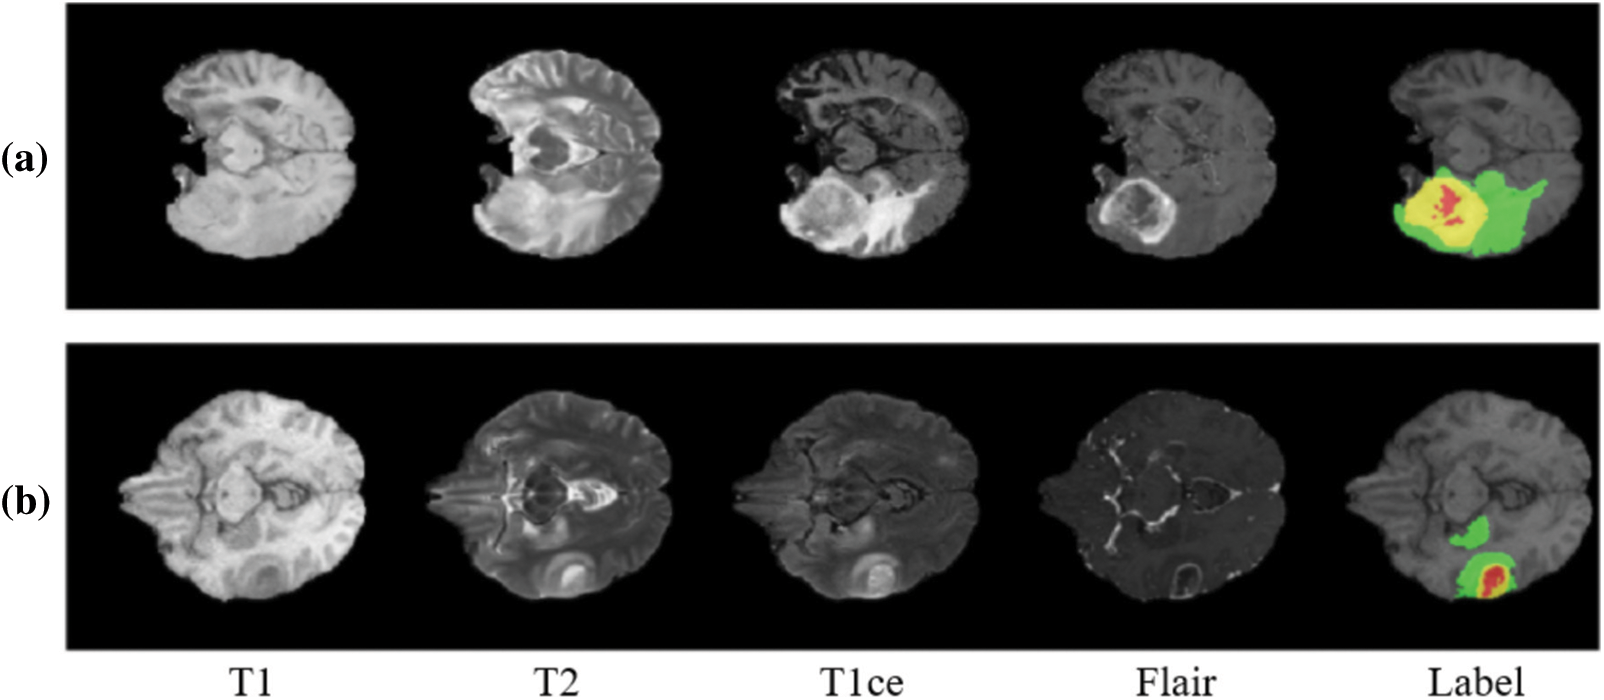

This model includes the standard data bases which are available open source namely Brain Tumor Segmentation Challenge (BraTS) 2017 and 2018 respectively. BraTS 2017 data set comprises of nearly 285 patients affected by glioma, where are these images are classified into High-Grade Gliomas (HGG) and Lower Grade Glioma (LGG) categories accordingly. There are a few patients whose condition cannot be determined, and segmentation cannot be performed. From the available information, the ground truth is computed for comparison with affected patients. The ground truth is a signature element which are derived by experts and doctors. The ground truth will later be used for annotations and the model can only be generated upon the server of BraTS. The labels of annotation are described as follows, increasing tumour, necrosis, edema or healthy tissue. All the processes are applicable to both the data sets and the number of inputs vary in 2018 data set accordingly. The following Fig. 1 illustrates the ground truth and other information of the obtained datasets.

Figure 1: Stages of brain tumour according to Brain Tumour Segmentation Challenge (BraTS) datasets